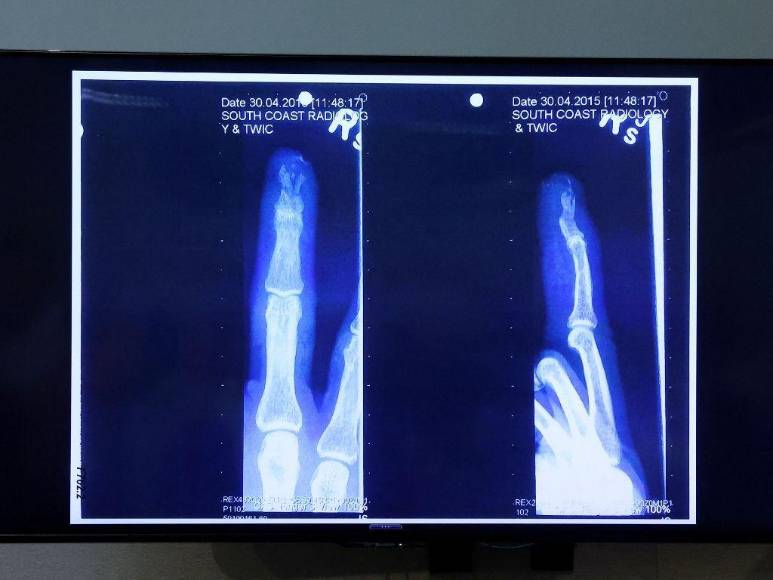

5. El dedo: Entre las muchas veces en que la pareja habría peleado destaca una en Australia, donde según la versión de él, ella le rebanó el dedo al lanzarle una botella de vodka que se rompió. Amber, por su parte, afirmó que él abusó sexualmente de ella con una botella esa misma noche.